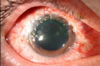

O que é anel de Fleischer?

Anel de ferro presente na base do ceratocone

Fonte: columbia eye